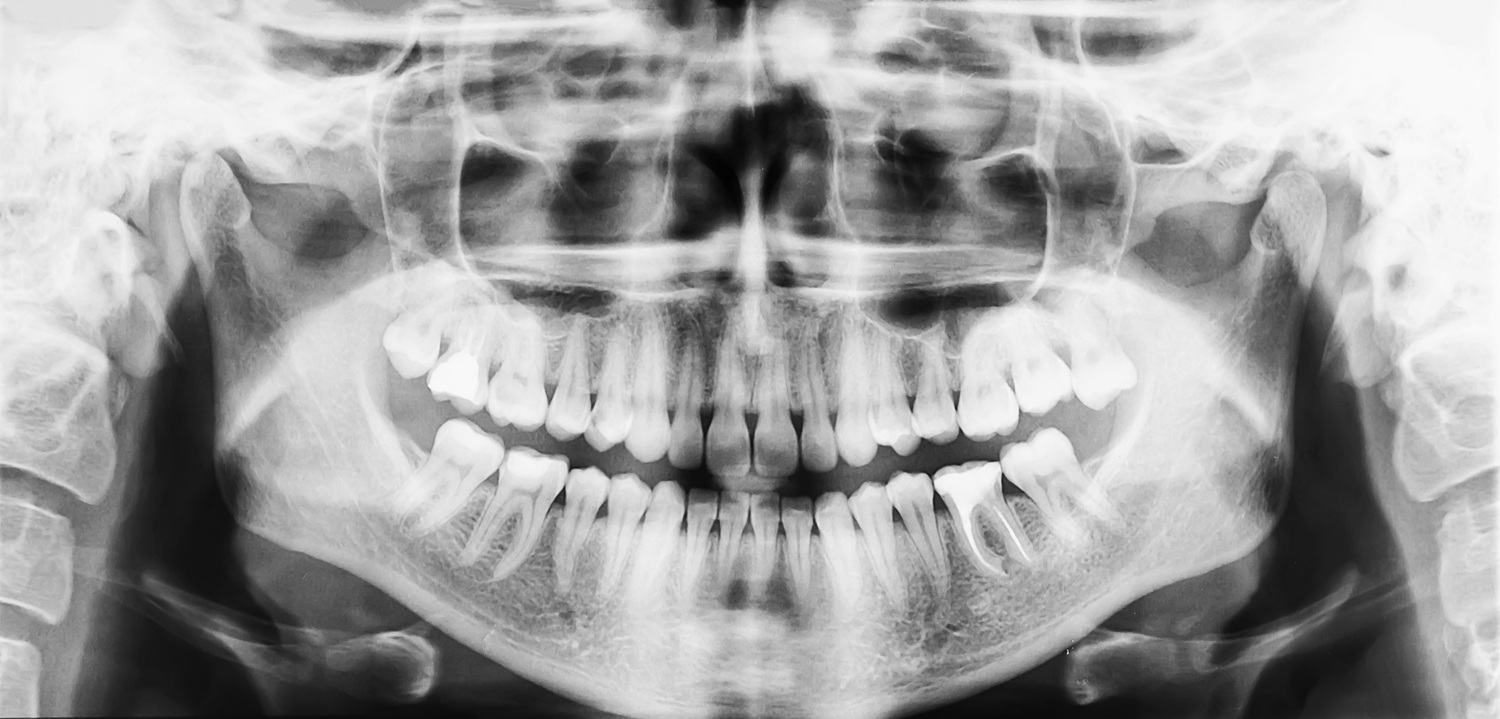

At Pearl Haus, digital imaging transforms how we approach root canal care — allowing us to move beyond traditional two-dimensional X-rays into a full, three-dimensional understanding of your dental anatomy. With 3D CBCT imaging, we can visualize even the most complex root structures, accurately assess the extent of infection, and customize every step of your treatment with precision.

This level of clarity allows us not only to plan treatment with confidence but to monitor healing over time — evaluating bone health and ensuring long-term stability after the procedure. CBCT is also essential when evaluating teeth that have previously undergone root canal therapy, as it can reveal lingering infection or incomplete healing that may not be visible with conventional imaging.

Before beginning any treatment, Dr. Wightman conducts high-resolution 3D CBCT scans and salivary testing to map the extent of the infection with exceptional clarity. These modern tools allow us to identify inflammation, bacterial strains, and hidden complications without relying on guesswork. Your therapy plan is then tailored to protect your health at every level, from local oral structures to your entire immune system.